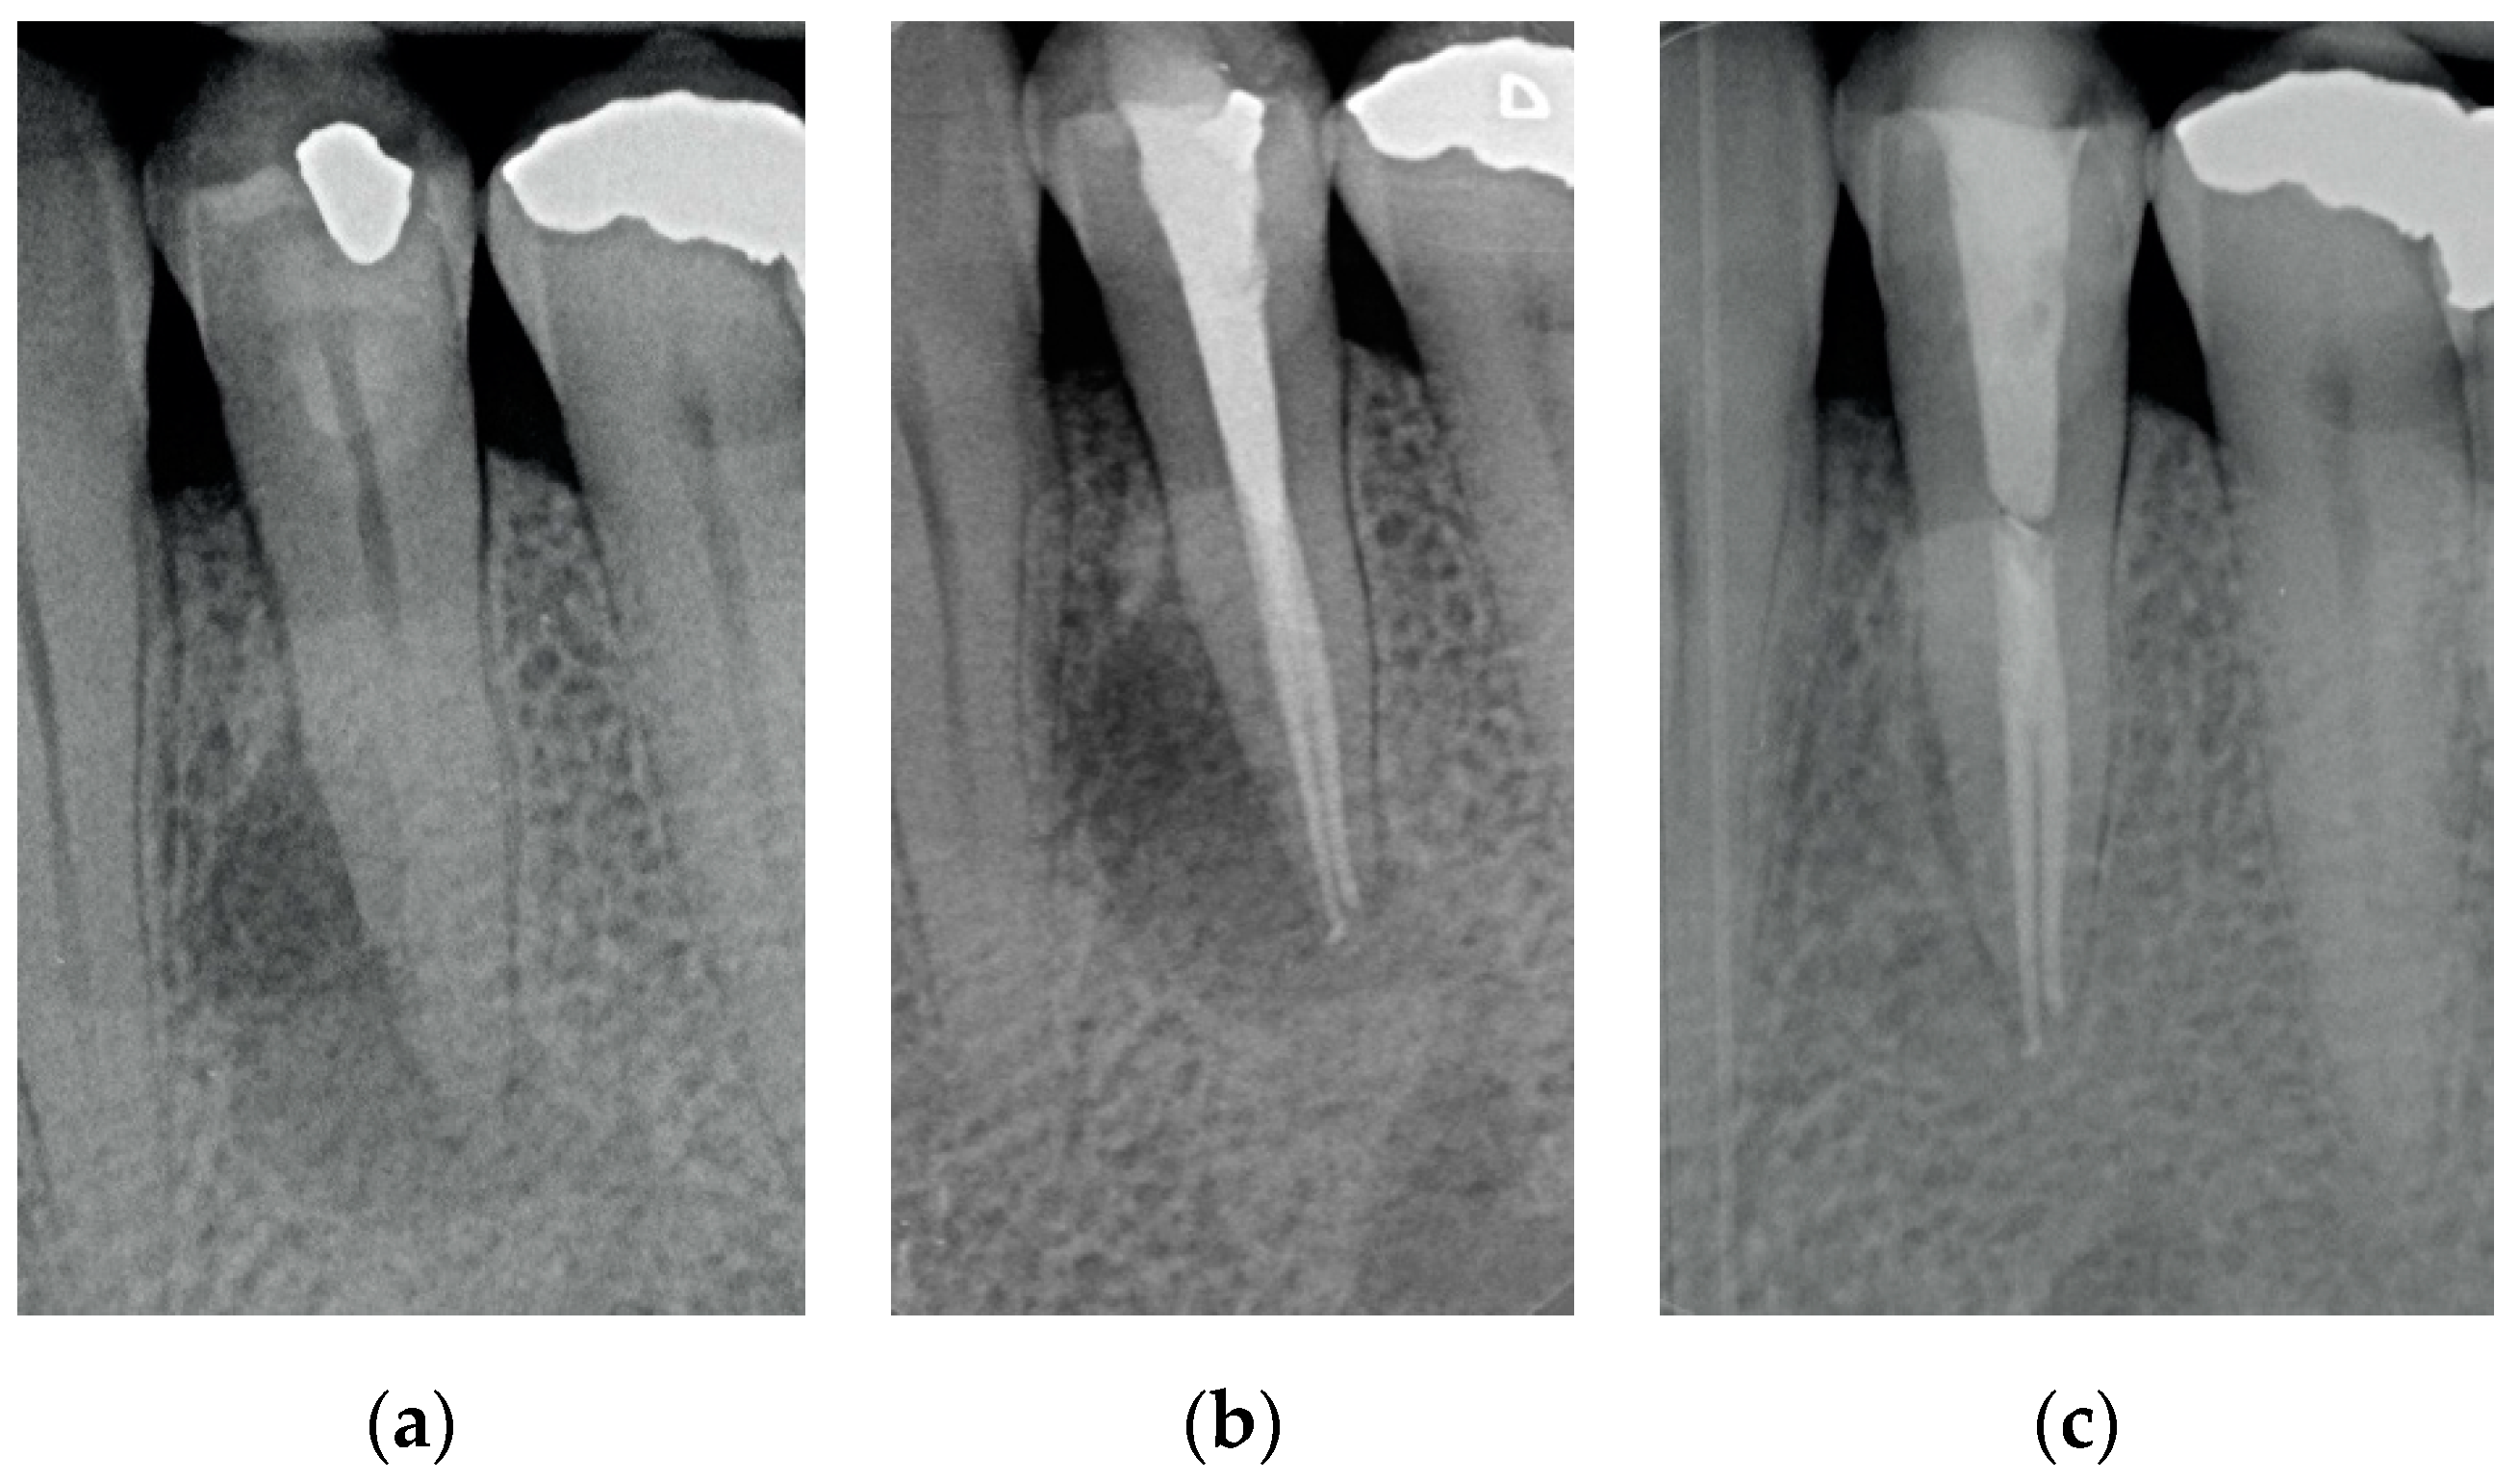

Figure 3. (a) A first lower molar with periapical lesion and in need to be retreated. (b) The molar immediately after being endodontically treated. Four canals (one in a radix entomolaris) were detected and treated. (c) The molar after 4 years. The good health of the periapical areas can be noted. The crown was restored with an adhesive esthetic onlay.

Results showed that 92.61% of ETT did not have any complications up to 18 years (Figure 1, Figure 2 and Figure 3).

Regarding the quality of root filling, 264 teeth (88.59%) showed good filling (Figure 1, Figure 2 and Figure 3) (gutta-percha at the radiologic apex), 22 roots (7.38%) short filling (shorter than 1 mm from the radiographic apex), and 12 (4.03%) long filling (longer than 1 mm of the radiographic apex).

The numbers of failures due to tooth fractures, endodontic, periodontal, or prosthodontic reasons, were limited to 22 of 298 ETT. Of the recorded failures, 14 were reported as repairable; eight were catastrophic failures and, consequently, needed root extraction. The success rate was around 92% (Figure 1, Figure 2 and Figure 3), the survival rate around 4.69%, and only less than 2.69% were irreversible failures. The success and survival rates of this clinical study were a little higher than several others [36,37,38]. Another important aspect related to the failure was the fact that irreversible failures mainly took over in the first two years and within the first 5 years, when cumulated as reversible and irreversible failures. It can be speculated that “biological” complications can come out rather quickly, and periodontal and prosthodontic complications in a longer time, but after 5 years of clinical service, it can be expected that an ETT can stay in clinical service for many more years.